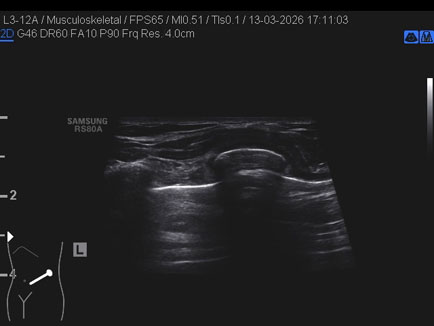

Data inserimento: 23/03/2026

Ecografia del: 13/03/2026

Strumento: Samsung

Sonda: Lineare

Commento all'esame: triplice frattura costale in ascellare anteriore sinistra in giovane dopo caduta con gli sci.

Conclusioni: triplice frattura costale (triple rib fracture).

Realizzazione: Dr. F. Pietro Tarini - Gubbio (PG)